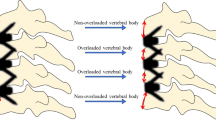

Junctional failures are clearly the result of an imbalance between anterior column compression forces and posterior column tension band strength. In other words, there is an excessive bending moment, a mechanism very similar to what is seen in vertebral compression fracture (VCF), a common pathology of the elderly population. VCF can occur after minor trauma or even fortuitously discovered on systematic X-rays. It has been shown that kyphotic patients have higher risk of VCF than the normal population [28].

Alf Nachemson and other authors previously reported that a lumbar functional spinal unit (SFU) can support a maximum axial weight of 500 kg, but a bending moment of only 20 Nm in flexion [29, 30]. Consequently, if the lever arm length is increased by only 10 cm, the maximal weight supported by the SFU will be reduced to 20 kg [30]. It is, thus, important to restore the anterior wall height of a fractured vertebra, to prevent the risk of additional adjacent fractures or domino effect (DE) [31] (Fig. 1). Disc height loss due to degeneration at several levels increases thoracic kyphosis and results in a similar biomechanical condition for the upper adjacent vertebra than a VCF.

The DE and the TS are directly related to the bending moment (BM), which is the product of the weight force (constant) and the arm length (variable) (Fig. 1). The arm length is the horizontal distance between the weight and the gravitational axis, and depends on the degree of kyphosis (greater kyphosis = greater lever arm).